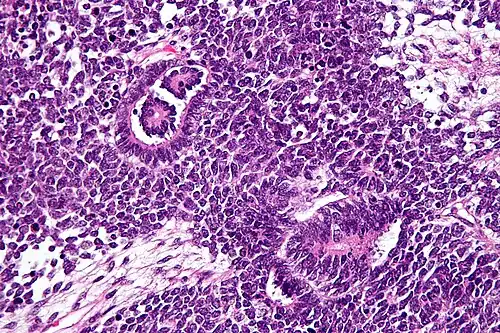

Las imágenes muestran las características de tres componentes: la pequeña y redonda maligno (azul), las células ~ 2 veces el tamaño de los linfocitos en reposo (componente de blastema); las estructuras tubulares o rosetas (componente epitelial) y estroma suelta paucicelular con células fusiformes.